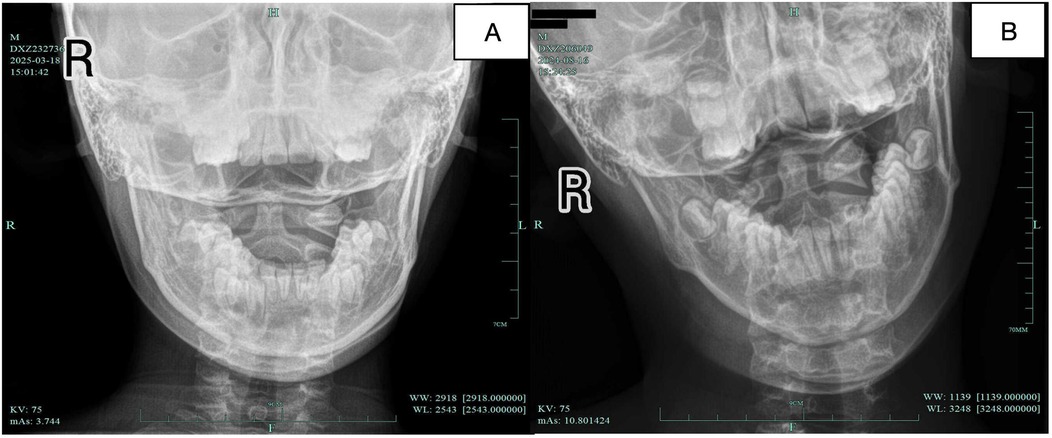

Background: Atlanto-axial rotatory subluxation (AARS) in pediatric patients is characterized by abnormal or restricted motion between the atlas and axis vertebrae, typically presenting with neck pain, limited mobility, torticollis, and muscle stiffness. Cervical atlanto-occipital joint X-ray in open-mouth position or CT scan reveals an atlanto-occipital distance (AOD) of 2mm < AOD < 5mm, or a bilateral atlanto-occipital lateral distance (B-LAD) ≥2mm. Although traditional manipulative and bone-setting techniques in Traditional Chinese Medicine have demonstrated clinical benefits, robust empirical evidence remains limited. Musculoskeletal ultrasound (MUSU), as a modern diagnostic modality, has gained popularity for assessing musculoskeletal disorders. Methods: This study utilized a randomized controlled trial design, where eligible patients diagnosed with AARS were, randomly assigned (1:1) to either a treatment group (gentle manipulative technique combined with continuous traction) or a control group (traction plus cervical collar immobilization). The treatment group received treatment twice daily, five days per week, for two weeks. The control group received the same traction protocol but wore a neck brace immediately after each traction treatment. The primary outcome measure was musculoskeletal ultrasound (MUSU) findings, while secondary outcomes include Visual Analogue Scale (VAS) pain scores and Neck Disability Index (NDI) scores. Both groups were assessed at baseline, post-treatment, two weeks, and six months after treatment. Discussion: The primary objective of this study aims to quantitatively assess the efficacy and safety of gentle manipulative therapy combined with continuous traction in pediatric AARS, using MUSU technology.